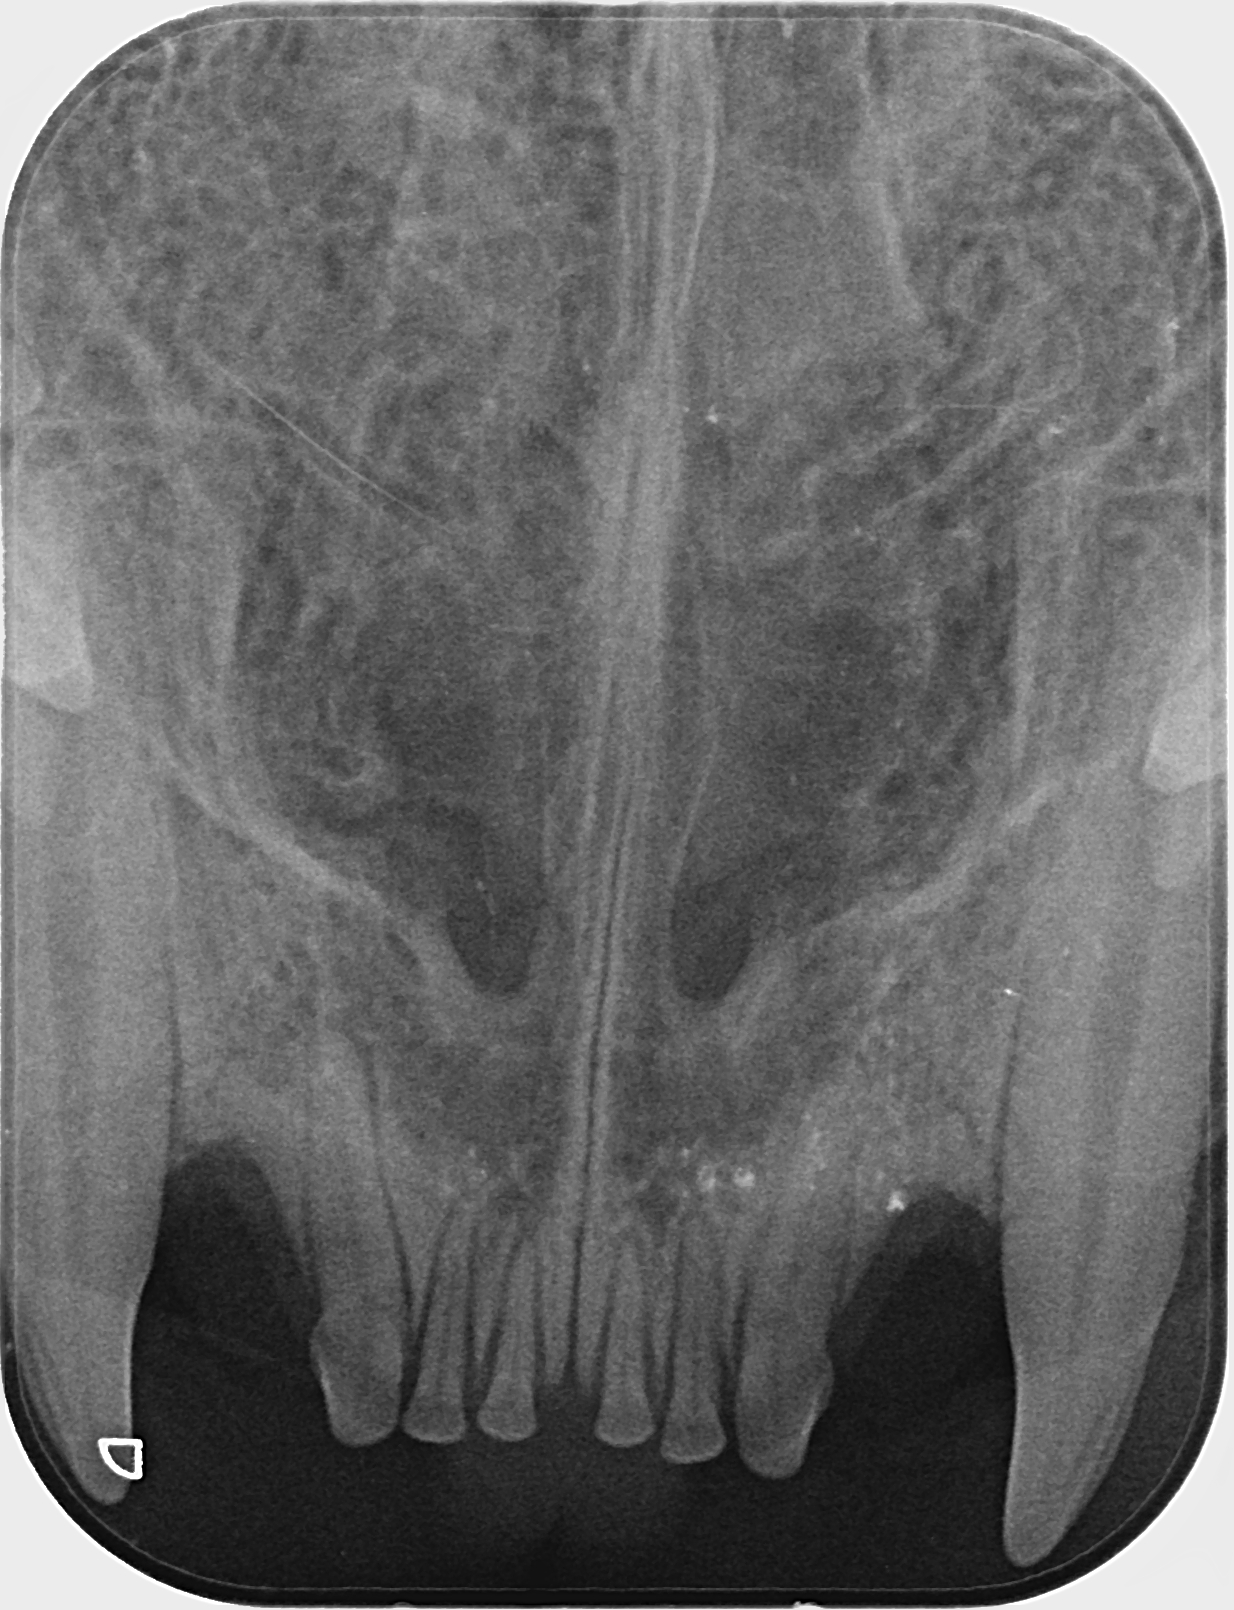

Kissan hampaat voivat näyttää päällisin puolin ihan hyvältä, mutta hampaiden juurissa voi olla piileviä ongelmia. Ainoa tapa selvittää, ovatko hampaat oikeasti kunnossa, on ottaa hammasröntgen.

IC Moggi Sikuri Sakari(Kilju) piipahti jo jonkin aikaaa sitten Amyvetissä hammahuollossa ja samassa kalusto pääsi kuviin. Tulos oli juuriaan myöten terveet hampaat. Hammaskiven poistoa pienesti ja ohjeeksi harjailla hampaita ahkerasti.

Ohessa muutama kuva malliksi.